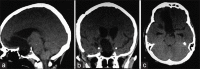

Case description: The authors report the case of a Brazilian 27-year-old man who presented with progressive vision loss during the last 4 years and serious bilateral keratoconus. We also review the epidemiological, clinical, radiological, pathological, and treatment features of the 12 reported cases. The patient developed left amaurosis and right temporal hemianopsia after undergoing bilateral corneal transplantation, which was detected during campimetry testing, and subsequently underwent magnetic resonance imaging, which revealed a huge hypophyseal tumor. Endocrinological evaluation revealed complete loss of pituitary function. The patient was referred to our department and underwent a two-step surgery (using transsphenoidal approach and cranio-orbital zygomatic approach) based on the diagnosis of an extraventricular central nervous system neurocytoma. Tumor removal was successful, and the patient was discharged at 3 weeks after admission to our department.